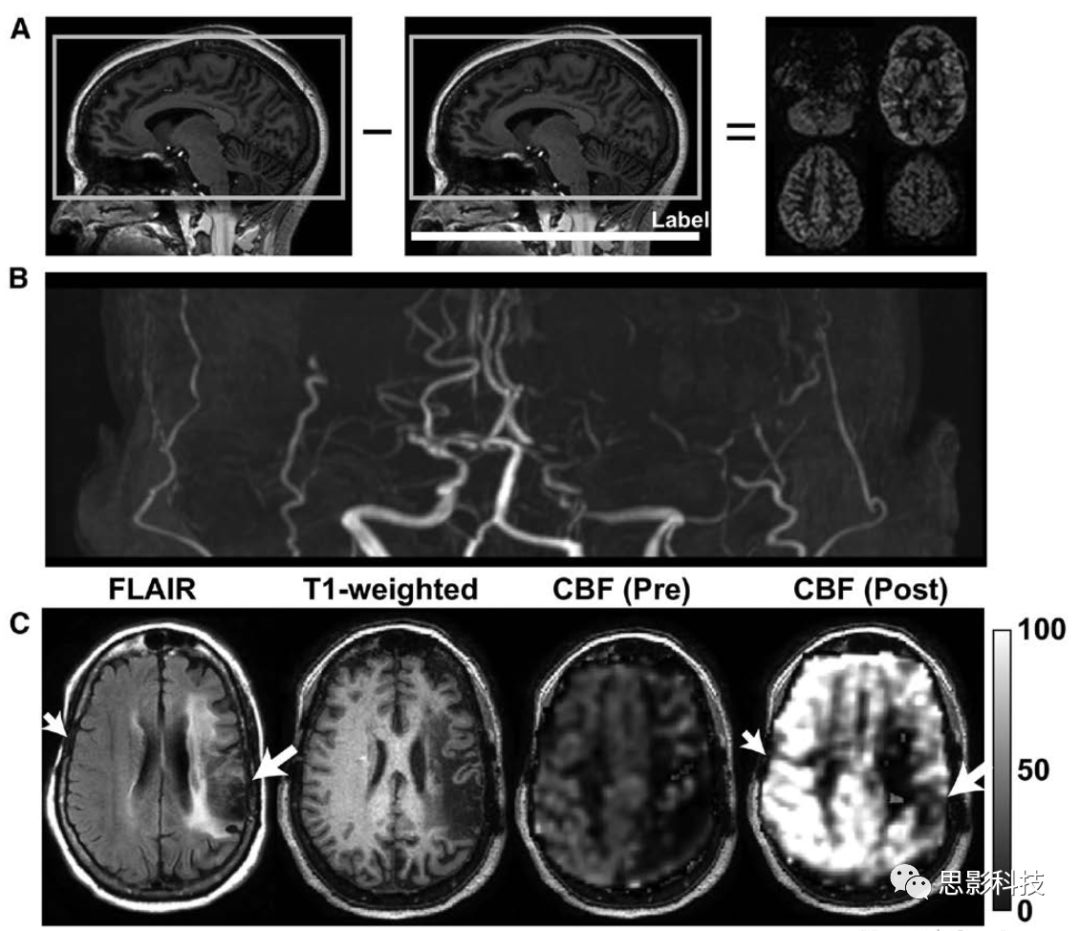

1動(dòng)脈自旋標(biāo)記磁共振成像(ASL-MRI)監(jiān)測外科血管重建。

A:在ASL-MRI中,使用單個(gè)(脈沖或連續(xù)的)或一系列(偽連續(xù)的)射頻脈沖對血液進(jìn)行磁性標(biāo)記,之后反轉(zhuǎn)的血液流入成像層面的毛細(xì)血管,與組織液交換,并衰減血管外水信號。通過將該圖像與其中未標(biāo)記血液的圖像進(jìn)行比較,可以獲得灌注加權(quán)圖。B:煙霧病合并左側(cè)頸內(nèi)動(dòng)脈床突上段閉塞、右側(cè)頸內(nèi)動(dòng)脈遠(yuǎn)端局灶性狹窄和雙側(cè)大腦中動(dòng)脈閉塞患者的飛行時(shí)間磁共振血管成像。

C:雙側(cè)腦硬膜動(dòng)脈貼敷術(shù)前后(左后22個(gè)月,右后16個(gè)月)ASL-MRI顯示術(shù)后腦血流量(CBF)改善情況。FLAIR:流體衰減反轉(zhuǎn)恢復(fù)。

越來越多的兒童使用ASL-MRI測量組織水平的CBF(1),可一致地顯示大腦中、前動(dòng)脈區(qū)域的低灌注模式,且常伴有后灌注。煙霧病的ASL結(jié)果非常復(fù)雜,因?yàn)檠旱竭_(dá)時(shí)間很長,根據(jù)成像參數(shù)的不同,可以表現(xiàn)為沒有信號或高信號。當(dāng)CMRO2的影響可忽略或發(fā)生微小變化時(shí),CBF增加,毛細(xì)血管和靜脈內(nèi)和周圍順磁性脫氧血紅蛋白相對于抗磁性氧合血紅蛋白的比例將減少,從而延長周圍水T2T2*,增加MRI信號(即血氧水平依賴[BOLD]效應(yīng))。因此,T2*加權(quán)序列可用于在影響血液和組織中二氧化碳和pH水平的代謝時(shí)進(jìn)行腦血管反應(yīng)性繪圖:使用藥物誘導(dǎo)的碳酸酐酶抑制劑(如乙酰唑胺)或呼吸刺激(如高碳酸血癥)。腦血管反應(yīng)性可能比基礎(chǔ)CBF更能預(yù)測預(yù)后,因?yàn)樗砻鹘M織實(shí)質(zhì)對灌注壓力變化作出反應(yīng)的能力。該方法已應(yīng)用于兒童煙霧病血管病變。

無創(chuàng)性ASL相較于有創(chuàng)灌注成像正受到越來越多的關(guān)注。ASL類似對比劑團(tuán)注增強(qiáng),使用單一或組合的射頻脈沖對動(dòng)脈血進(jìn)行磁性標(biāo)記(1)。標(biāo)記后,動(dòng)脈血流入大腦,在毛細(xì)血管水平與組織水交換,減弱組織液信號。通過將該標(biāo)記圖像與未標(biāo)記動(dòng)脈血的圖像進(jìn)行比較,可以獲得灌注加權(quán)圖像,并應(yīng)用流動(dòng)修正Bloch方程將其轉(zhuǎn)換為CBF(單位:ml(min·100g))。而該方法的挑戰(zhàn)在于怎么縮短獲得覆蓋全腦圖像所需的掃描時(shí)間,同時(shí)在血液到達(dá)時(shí)間>2秒的情況下不影響定量準(zhǔn)確性和成像質(zhì)量。利用三維讀出器、陣列接收線圈和標(biāo)準(zhǔn)發(fā)射線圈,可在5分鐘內(nèi)完成2-4 mm各向同性空間分辨率的ASL序列。已在成人和兒童中介紹了ASL采集和分析過程,包括與半暗帶區(qū)的相關(guān)性。